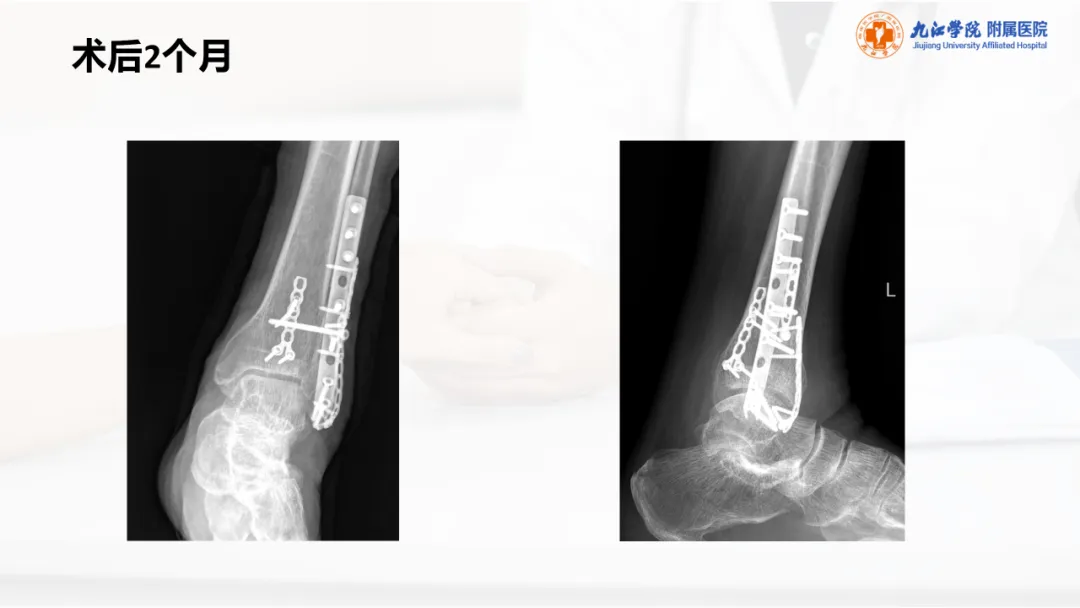

当前位置:首页>PPT>PPT纯享:陈旧性踝关节骨折的治疗案例(内附文献推荐)

PPT纯享:陈旧性踝关节骨折的治疗案例(内附文献推荐)